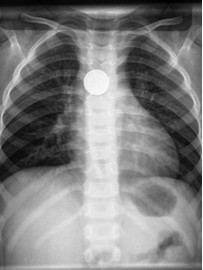

自动玩具因为受到孩子们的喜欢,被家长们源源不断的买回家中, 孩子因误吞玩具 ,和家中纽扣纽扣电池就医的急诊也不断增多。

如果纽扣电池停留在食道中,不能及时取出,会造成严重伤害,甚至死亡。

因为电池被食道里的粘液连接成了一个通电的回路,电池放电,粘液在电流的作用下,发生化学发应,产生出了富含氢氧化物的碱性溶液,腐蚀人体组织。